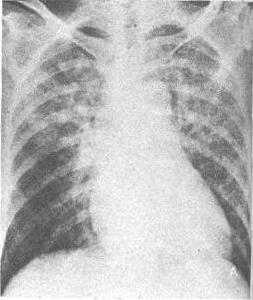

1、發病期:症狀不典型,患者呼吸短促,有時表現為焦慮不安。體檢可見皮膚蒼白濕冷、心率增快。X 線檢查見肺門附近可有典型薄霧狀或“蝴蝶狀”陰影。

心臟解剖圖2、有急性肺水腫表現,如突然胸悶、氣急、端坐呼吸、面色蒼白、口唇發紺、陣咳、咯出大量粉紅色泡沫痰、嚴重時咯血,聽診兩肺有廣泛濕性囉音和哮鳴音;x線檢查可見以肺門為中心的蝴蝶狀陰影。

1、X 線胸片 可見肺門有蝴蝶形態片狀陰影並向周圍擴展的肺水腫徵象,心界擴大,心尖搏動減弱等。